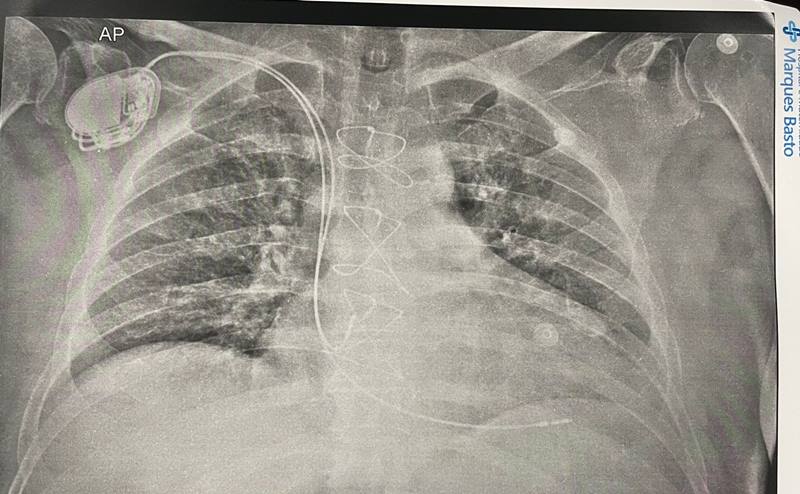

Foi realizado neste sábado (15), no Hospital Marques Basto a primeira cirurgia do norte do Piauí para implantação de marcapasso. O procedimento foi realizado pela equipe de médicos Dr. Dib Filho, Dra. Daniela Machado, Dr. Rafael Jung, Dr. Samuel Darcy, técnico de marcapasso Arildo Campelo e por técnicos do HMMB. A cirurgia foi considerada um sucesso. Continua depois da publicidade

Com o implante de marcapasso sendo realizado em Parnaíba, no Hospital, também já é possível realizar o implante do CDI (cardiodesfibridor implantável) e ressincronizador.